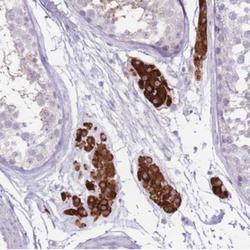

- Immunohistochemistry: C19orf69 Antibody [NBP2-30800] - Staining of human testis shows strong cytoplasmic positivity in Leydig cells.